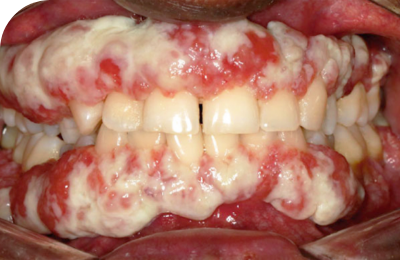

Mouth

32% of people with PLGD-1 experience lesions on the gums.5

Lesions on the gums are typically painless and are often described as white spots around the teeth that won’t come off. Left untreated, lesions can lead to gum and tooth loss.2

Ligneous gingivitis caused by congenital plasminogen deficiency type 1, manifesting as gum lesions Respiratory tract lesions in plasminogen deficiency type 1 patient Skin lesions on arm